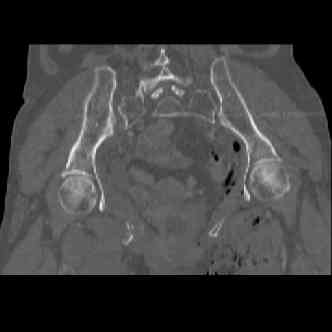

Отправитель: dan schlatterer 12 Июнь 2007, 04:47

attached are several CT cuts. please let me know if you need more. the CT is pre-pelvic ex-fix placement.

Thank you.

Отправитель: Chip Routt 12 Июнь 2007, 04:53

I wouldn't plate the front.

But I would add screws posteriorly.